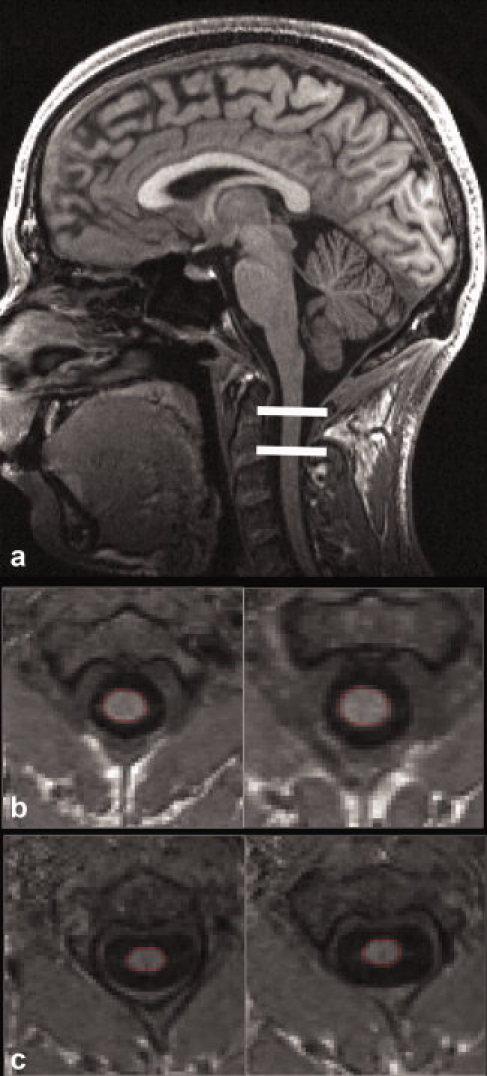

To investigate whether a 3D-modified driven equilibrium Fourier transform (MDEFT)-based acquisition protocol established for brain morphometry also yields reliable information about the cross-sectional spinal cord area (SCA).

Images of brain and cervical cord of 10 controls and eight subjects with spinal cord injury (SCI) were acquired with the 3D-MDEFT-based imaging protocol and an 8-channel receive head coil. The new protocol was validated by two observers 1) comparing the SCA measured with the standard acquisition protocol (3D magnetization-prepared rapid acquisition gradient echo [MPRAGE] and dedicated spine coil) and the new protocol; and 2) determining the scan-rescan reproducibility of the new protocol.

Scan-rescan reproducibility of SCA measurements with the MDEFT approach showed a similar precision for both observers with standard deviation (SD) <4.5 mm(2) and coefficient of variation (CV) ≤5.1%. Analysis of variance (ANOVA) revealed a main effect of observer and interaction between observer and scan protocol that could be primarily attributed to a small observer bias for MPRAGE (difference in SCA <2.1 mm(2)). No bias was observed for 3D-MDEFT vs. 3D-MPRAGE.

The 3D-MDEFT method allows for robust unbiased assessment of SCA in addition to brain morphology.

研究基于三维修正驱动平衡傅里叶变换(MDEFT)的脑形态测量采集方案是否也能提供关于脊髓横截面积(SCA)的可靠信息。

10 例健康对照者和 8 例脊髓损伤(SCI)患者的脑和颈髓图像采用基于 3D-MDEFT 的成像方案和 8 通道接收线圈进行采集。新方案通过两位观察者进行了验证:1)比较标准采集方案(3D 磁化准备快速获取梯度回波[MPRAGE]和专用脊柱线圈)和新方案测量的 SCA;2)确定新方案的扫描-再扫描可重复性。

MDEFT 方法测量 SCA 的扫描-再扫描可重复性对于两位观察者具有相似的精度,标准偏差(SD)<4.5mm2,变异系数(CV)≤5.1%。方差分析(ANOVA)显示观察者和扫描方案之间存在主要交互作用,这主要归因于 MPRAGE 的观察者偏倚较小(SCA 差异<2.1mm2)。与 3D-MPRAGE 相比,3D-MDEFT 没有观察到偏差。

除了脑形态学外,3D-MDEFT 方法还可以对 SCA 进行稳健、无偏的评估。